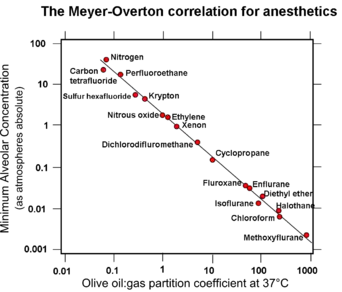

Lipid solubility-anaesthetic potency correlation (the Meyer-Overton correlation)

A nonspecific mechanism of general anaesthetic action was first proposed by Emil Harless and Ernst von Bibra in 1847.[9] They suggested that general anaesthetics may act by dissolving in the fatty fraction of brain cells and removing fatty constituents from them, thus changing activity of brain cells and inducing anaesthesia. In 1899 Hans Horst Meyer published the first experimental evidence of the fact that anaesthetic potency is related to lipid solubility.[10][11] Two years later a similar theory was published independently by Charles Ernest Overton.[12]

Meyer compared the potency of many agents, defined as the reciprocal of the molar concentration required to induce anaesthesia in tadpoles, with their olive oil/water partition coefficient. He found a nearly linear relationship between potency and the partition coefficient for many types of anaesthetic molecules such as alcohols, aldehydes, ketones, ethers, and esters. The anaesthetic concentration required to induce anaesthesia in 50% of a population of animals (the EC50) was independent of the means by which the anaesthetic was delivered, i.e., the gas or aqueous phase.[10][11][13]

Meyer and Overton had discovered the striking correlation between the physical properties of general anaesthetic molecules and their potency: the greater the lipid solubility of a compound in olive oil, the greater its anaesthetic potency.[13] This correlation is true for a wide range of anaesthetics with lipid solubilities ranging over 4-5 orders of magnitude if olive oil is used as the oil phase. This correlation can be improved considerably in terms of both the quality of the correlation and the increased range of anaesthetics if bulk octanol[14] or a fully hydrated fluid lipid bilayer[15][16][17][18] is used as the "oil" phase. It was also noted that volatile anaesthetics are additive in their effects (a mixture of a half dose of two different volatile anaesthetics gave the same anaesthetic effect as a full dose of either drug alone).